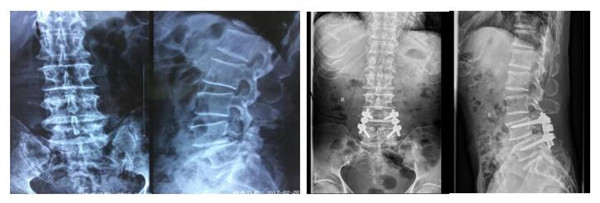

术前(左图)、术后(右图) X线对比显示腰4滑脱椎体完全复位,内固定位置良好。